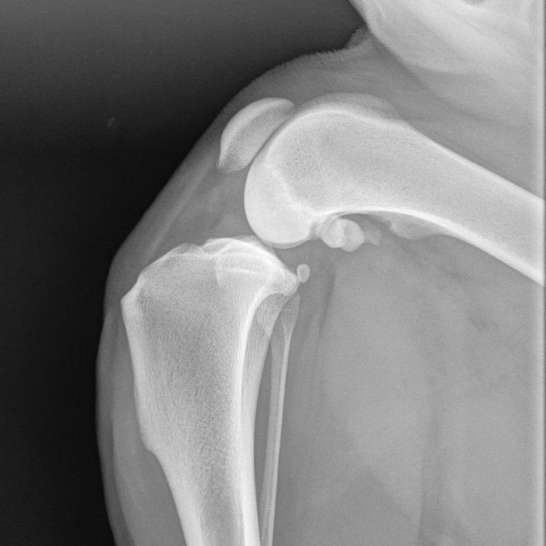

Erkrankungen rund um das Knie beim Hund

- Kreuzbandriss

- Meniscopathien

- OCD

- Patellaluxation

Ursachen, Op Techniken, Prognosen.